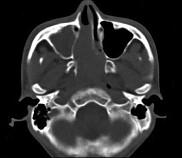

问题 男,20岁,头痛、鼻塞、鼻出血,CT如图所示,最可能诊断为()

选项 A.鼻咽癌 B.巨大的鼻息肉 C.鼻咽纤维血管瘤 D.鼻咽神经纤维瘤 E.鼻咽腺样体增生

答案 C